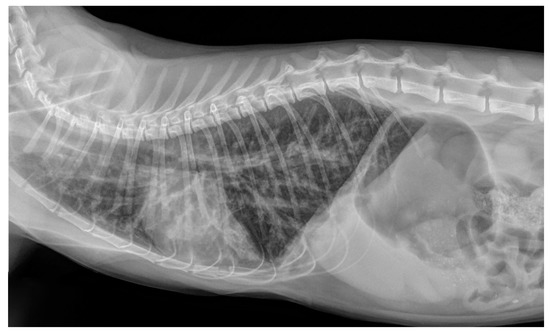

2.2. Radiographic Findings

- Crisi, P.E.; Aste, G.; Traversa, D.; Di Cesare, A.; Febo, E.; Vignoli, M.; Santori, D.; Luciani, A.; Boari, A. Single and mixed feline lungworm infections: Clinical, radiographic and therapeutic features of 26 cases (2013-2015). J. Feline Med. Surg. 2017, 19, 1017–1029. [Google Scholar] [CrossRef] [PubMed]

- Febo, E.; Crisi, P.E.; Traversa, D.; Luciani, A.; Di Tommaso, M.; Pantaleo, S.; Santori, D.; Di Cesare, A.; Boari, A.; Terragni, R.; et al. Comparison of clinical and imaging findings in cats with single and mixed lungworm infection. J. Feline Med. Surg. 2019, 21, 581–589. [Google Scholar] [CrossRef]

- Genchi, M.; Ferrari, N.; Fonti, P.; De Francesco, I.; Piazza, C.; Viglietti, A. Relation between Aelurostrongylus abstrusus larvae excretion, respiratory and radiographic signs in naturally infected cats. Vet. Parasitol. 2014, 206, 182–187. [Google Scholar] [CrossRef]

- Lacava, G.; Zini, E.; Marchesotti, F.; Domenech, O.; Romano, F.; Manzocchi, S.; Venco, L.; Auriemma, E. Computed tomography, radiology and echocardiography in cats naturally infected with Aelurostrongylus abstrusus. J. Feline Med. Surg. 2017, 19, 446–453. [Google Scholar] [CrossRef]

- Dennler, M.; Bass, D.A.; Gutierrez-Crespo, B.; Schnyder, M.; Guscetti, F.; Di Cesare, A.; Deplazes, P.; Kircher, P.R.; Glaus, T.M. Thoracic computed tomography, angiographic computed tomography, and pathology findings in six cats experimentally infected with aelurostrongylus abstrusus. Vet. Radiol. Ultrasound 2013, 54, 459–469. [Google Scholar] [CrossRef]